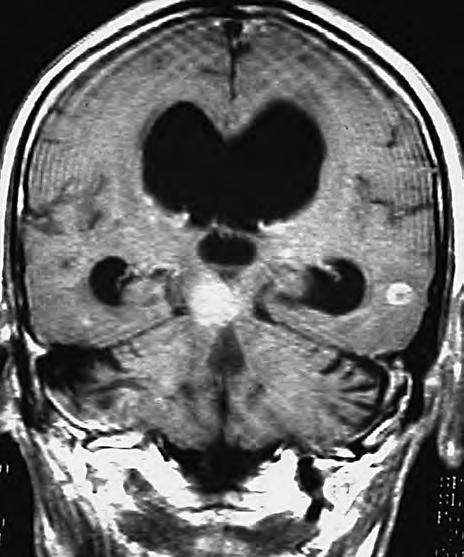

Obr. 1.4 Miliární metastázy mozku bronchogenního karcinomu s okluzí aquaeduktu a hydrocefalem. MR zobrazení v koronárním řezu v T1 váženém čase po aplikaci kontrastní látky i.v. Bílá šipka ukazuje v tektu umístěnou metastázu blokující svou expanzí aquaedukt.

Metastázy mohou vCNS vytvořit jak solitární, tak ivícečetná ložiska, mohou však také infiltrovat meningy (bronchogenní karcinom, karcinomy prsu ižaludku).

Obr. 1.5 Miliární metastázy mozku bronchogenního karcinomu s okluzí aquaeduktu a hydrocefalem. MR zobrazení v sagitálním řezu v T1 váženém čase po aplikaci kontrastní látky i.v. Bílá šipka ukazuje v tektu umístěnou metastázu blokující svou expanzí aquaedukt.